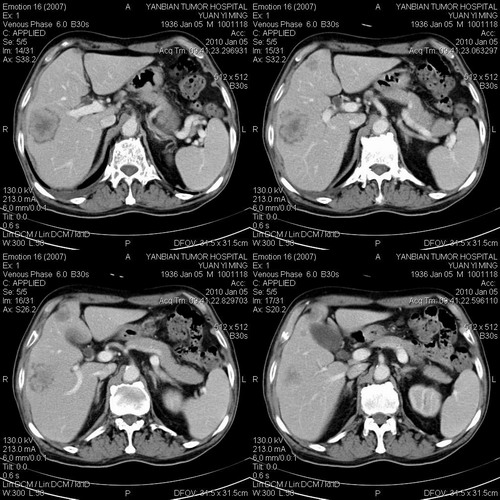

标题: CT24024:男,74岁。体检超声发现肝内多发占位性病变四天。 [打印本页]

标题: CT24024:男,74岁。体检超声发现肝内多发占位性病变四天。

肝癌肝内转移,胃壁增厚,胃癌不能排除

建议查afp。考虑多发结节型肝癌。

考虑多发结节性肝癌。

1)考虑肝脏恶性肿瘤(转移瘤?)。2)肝外胆管轻度扩张。3)左肾小囊肿。